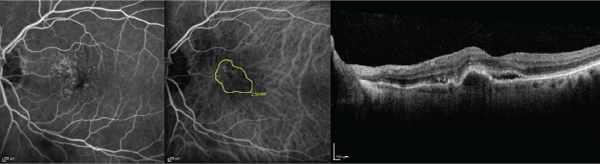

Figure 2: The fluorescein angiography (left), indocyanine green angiography (middle), and optical coherence tomography (right) images are displayed in the same

subject as Figure 1 after 8 consecutive monthly bevacizumab injections and 4 aflibercept injections. The Snellen visual acuity has decreased to 20/60. Note the

enlargement in choroidal neovascularization surface area from baseline.

Figure 3: The fluorescein angiography (left), indocyanine green angiography (middle), and optical coherence tomography (right) images are displayed in the same

subject as Figures 1 and 2 after 4 biweekly bevacizumab injections followed by 3 monthly bevacizumab injections. The Snellen visual acuity has improved to 20/30.

Note the reduction in choroidal neovascularization surface area from Figure 2.

There were 88.2 % (15/17) of subjects that had a reduction in CNV size at the 6-month follow-up evaluation after initiating biweekly bevacizumab. CNV size on ICG angiography enlarged by 33 % or more in 29.4 % (5/17) from treatment naivety until the evaluation in which biweekly bevacizumab therapy was decided upon. CNV size on ICG angiography decreased by 33 % or more in 47.0 % (8/17) at the 6-month follow-up evaluation after initiating biweekly bevacizumab; CNV size on ICG angiography decreased by 33 % or more in 0 % from treatment naivety until the evaluation in which biweekly bevacizumab therapy was decided upon (Figures 1-3).